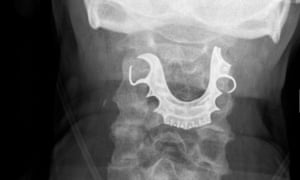

RPD lodged in the Larynx

A man who turned up in the ER coughing up blood and having

difficulty swallowing has surprised doctors who discovered he had false

teeth lodged in his larynx.